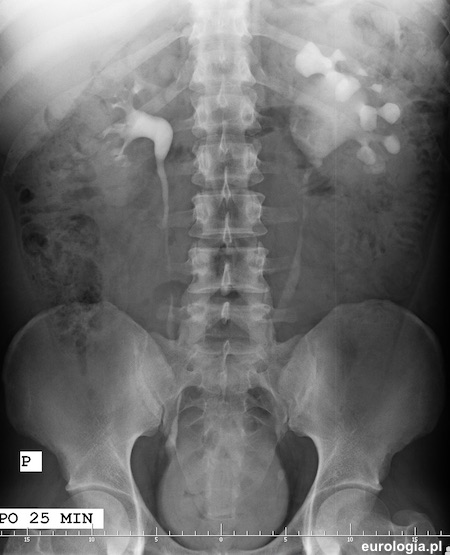

Urografia - kamica moczowodowa lewostronna i naczynie dodatkowe lewej nerki

Zdjęcie urograficzne po 25 minutach. Po stronie lewej widoczny poszerzony układ kielichowo miedniczkowy. Połączenie miedniczkowo moczowodowe po stronie lewej kątowo zagięte - obraz sugeruje naczynie dodatkowe lewej nerki.

Zółtą strzałką zaznaczono złóg w lewym moczowodzie o wymiarach 8,7x4,7 milimetra.